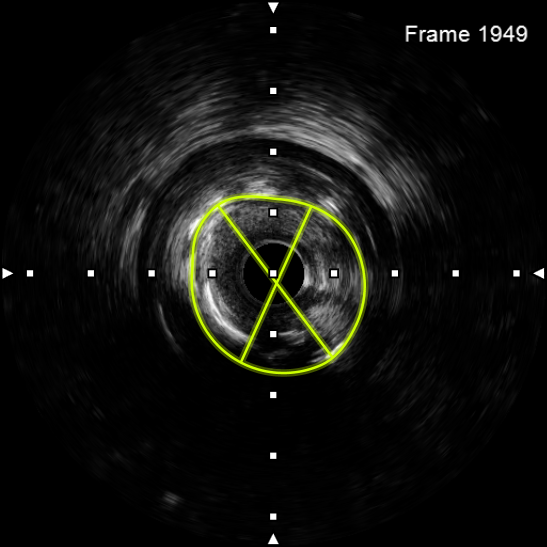

该患者入院后,完善相关检查并再次建议行CABG治疗,但家属仍拒绝,遂考虑再次行PCI手术干预。冠脉造影提示患者冠脉右冠状动脉中段70-95%再狭窄,左主干末端80%狭窄,前降支原支架中远段 80-95%再狭窄,回旋支完全闭塞,急需手术尽快解决冠脉血流灌注问题,否则随时有生命风险,但患者多处支架内/节段内再狭窄,造影提示钙化明显,外院已尝试无法扩张,经手术团队充分讨论后,计划在IABP支持下,先进行右冠状动脉干预,利用IVUS精准评估原支架再狭窄部位情况,采用旋磨或Shockwave冲击波球囊处理无法扩张的病变部位,右冠处理后择期进行左冠状动脉干预。在制定了详尽的手术计划后,手术团队首先对患者的右冠状动脉行IVUS检查,结果提示该患者右冠中段支架局部膨胀不良,局部支架面积6.67mm²,管腔内多处可见钙化小结及270°以上钙化,IVUS钙化积分达3分。由于膨胀不良处原支架后方可见钙化斑块,常规旋磨效果不佳,对于此类钙化病变,IVL处理是最佳方案。手术团队对近端采取棘突球囊及高压球囊进行扩张,采用Guidezilla辅助下输送3.0mmx12mm Shockwave冲击波球囊于右冠钙化处进行冲击波钙化斑块碎裂术,通过IVUS证实支架内的新生钙化病变得到松解,原膨胀不良部位支架面积达到7.76mm²,后经过高压球囊充分预处理,顺利完成右冠支架植入,术后复查右冠原膨胀不良部位支架面积9.17mm²。

图4 3.0 Shockwave处理后可见钙化断裂 高压球囊验证膨胀良好